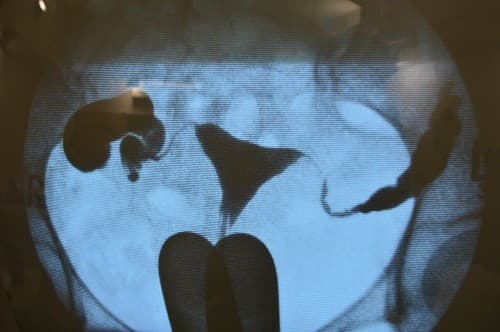

Chụp tử cung vòi trứng là phương pháp sử dụng tia X để kiểm tra ống dẫn trứng có thông suốt hay bị tắc nghẽn và xem được hình dạng buồng tử cung có bình thường hay không.

Dung dịch cản quang sẽ đi vào hai ống dẫn trứng, và vào ổ bụng nếu ống dẫn trứng thông suốt.

Trong thủ thuật này, người bệnh cần chụp phim sẽ nằm theo tư thế sản khoa. Tiếp đó bác sĩ sẽ chèn một dụng cụ (mỏ vịt) vào âm đạo, lạc sạch cổ tử cung và có thể thuốc tê tại chỗ vào cổ tử cung để giảm sự khó chịu. Sau đó rút mỏ vịt và đặt một ống thông vào lỗ cổ tử cung rồi bơm vào vào buồng tử cung một ít dung dịch có chứa chất cản quang (Iot).

Người bệnh được đặt dưới máy chụp X quang và tiến hành chụp, có thể sẽ phải thay đổi nhiều tư thế để chụp được hình ảnh ở các góc độ khác nhau. Dung dịch cản quang sẽ đi vào hai ống dẫn trứng, và vào ổ bụng nếu ống dẫn trứng thông suốt. Những bất thường trong lòng tử cung cũng có thể phát hiện nhờ phim X quang.